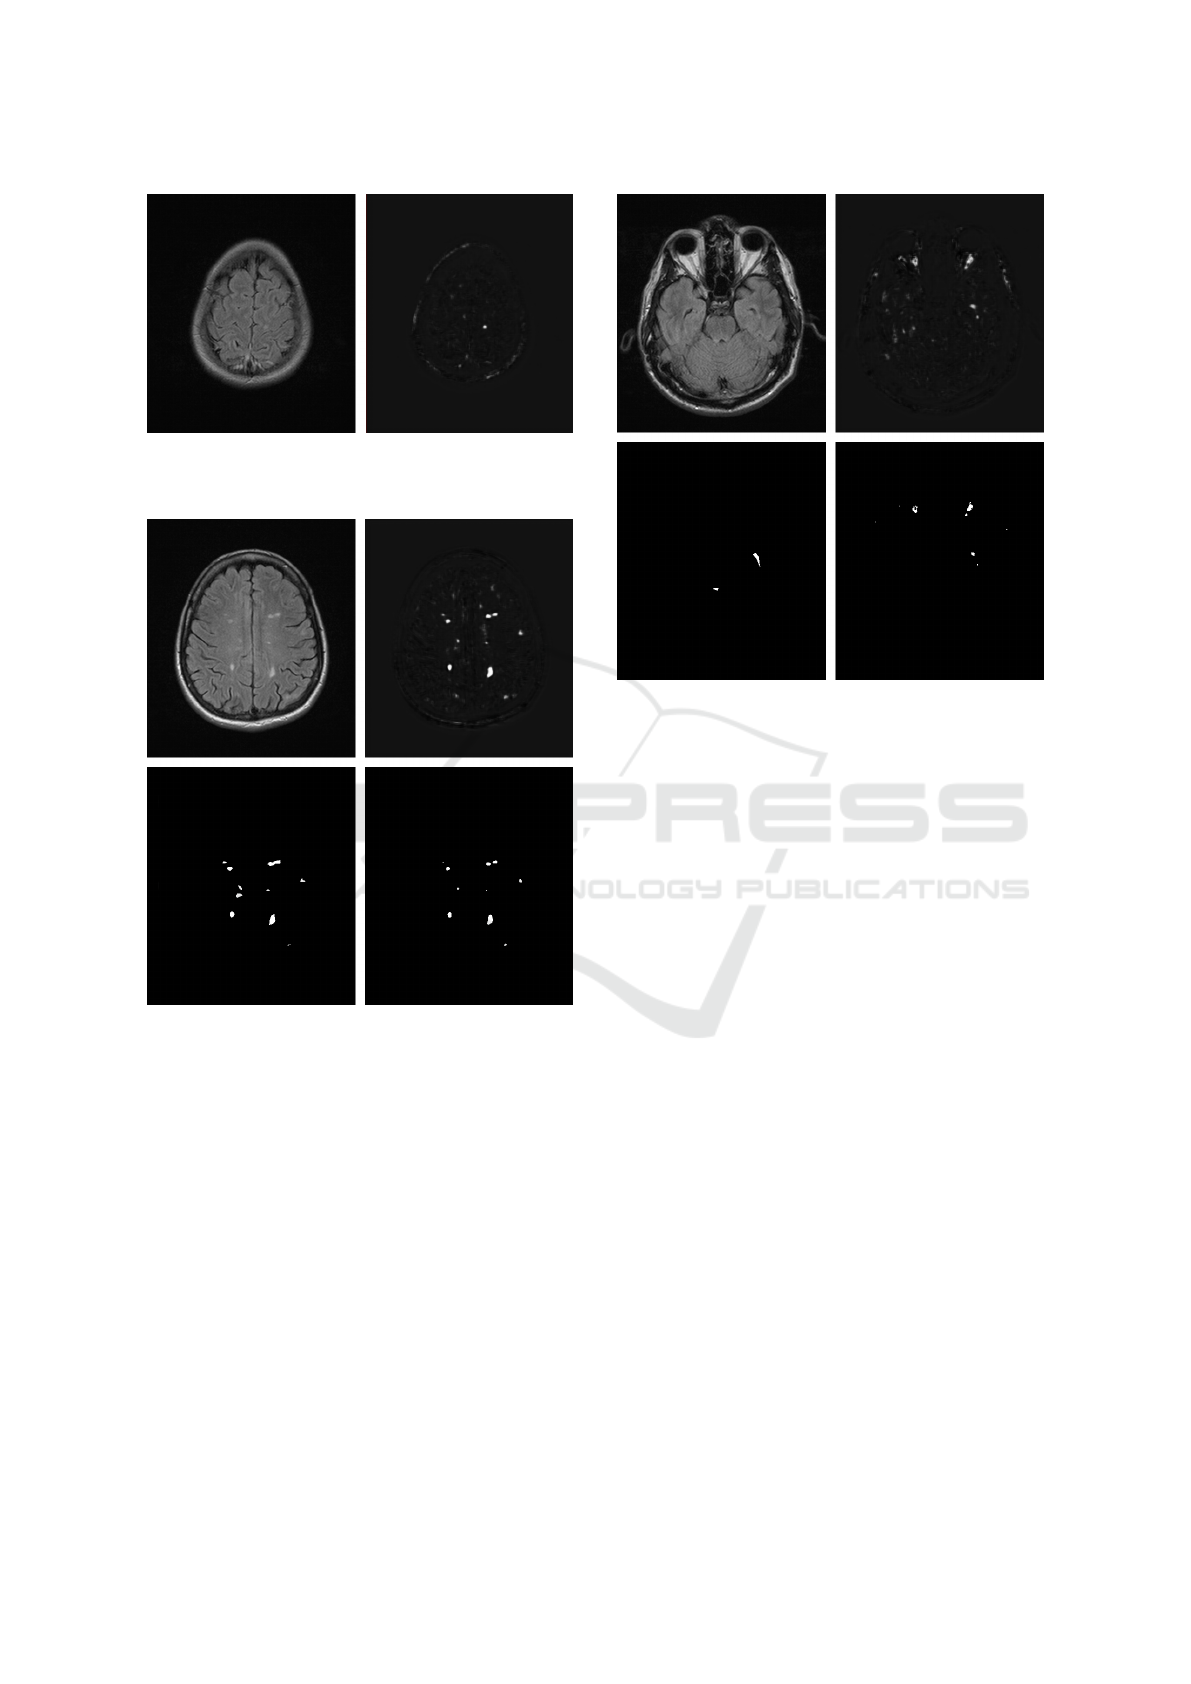

The best of the proposed models provided F-

measure of 55% on the test set. This value itself

is way from the perfect score. However, getting the

general location of the plaque and slightly imprecise

shape already reduces the value below 100%. The

gold standard consisted of approximate polygons, so

repeating it precisely is virtually impossible. More

significantly problematic factors were related to the

false positives at the large bright areas, such as overly

activated points near the temporal bones and optic

nerves. Another common source of errors was re-

lated to mistakenly activated small regions (noise un-

related to the demyelinating plaques). On the other

hand, presence of selected points in the general area

of demyelinating plaques is a notable advantage of the

suggested model.